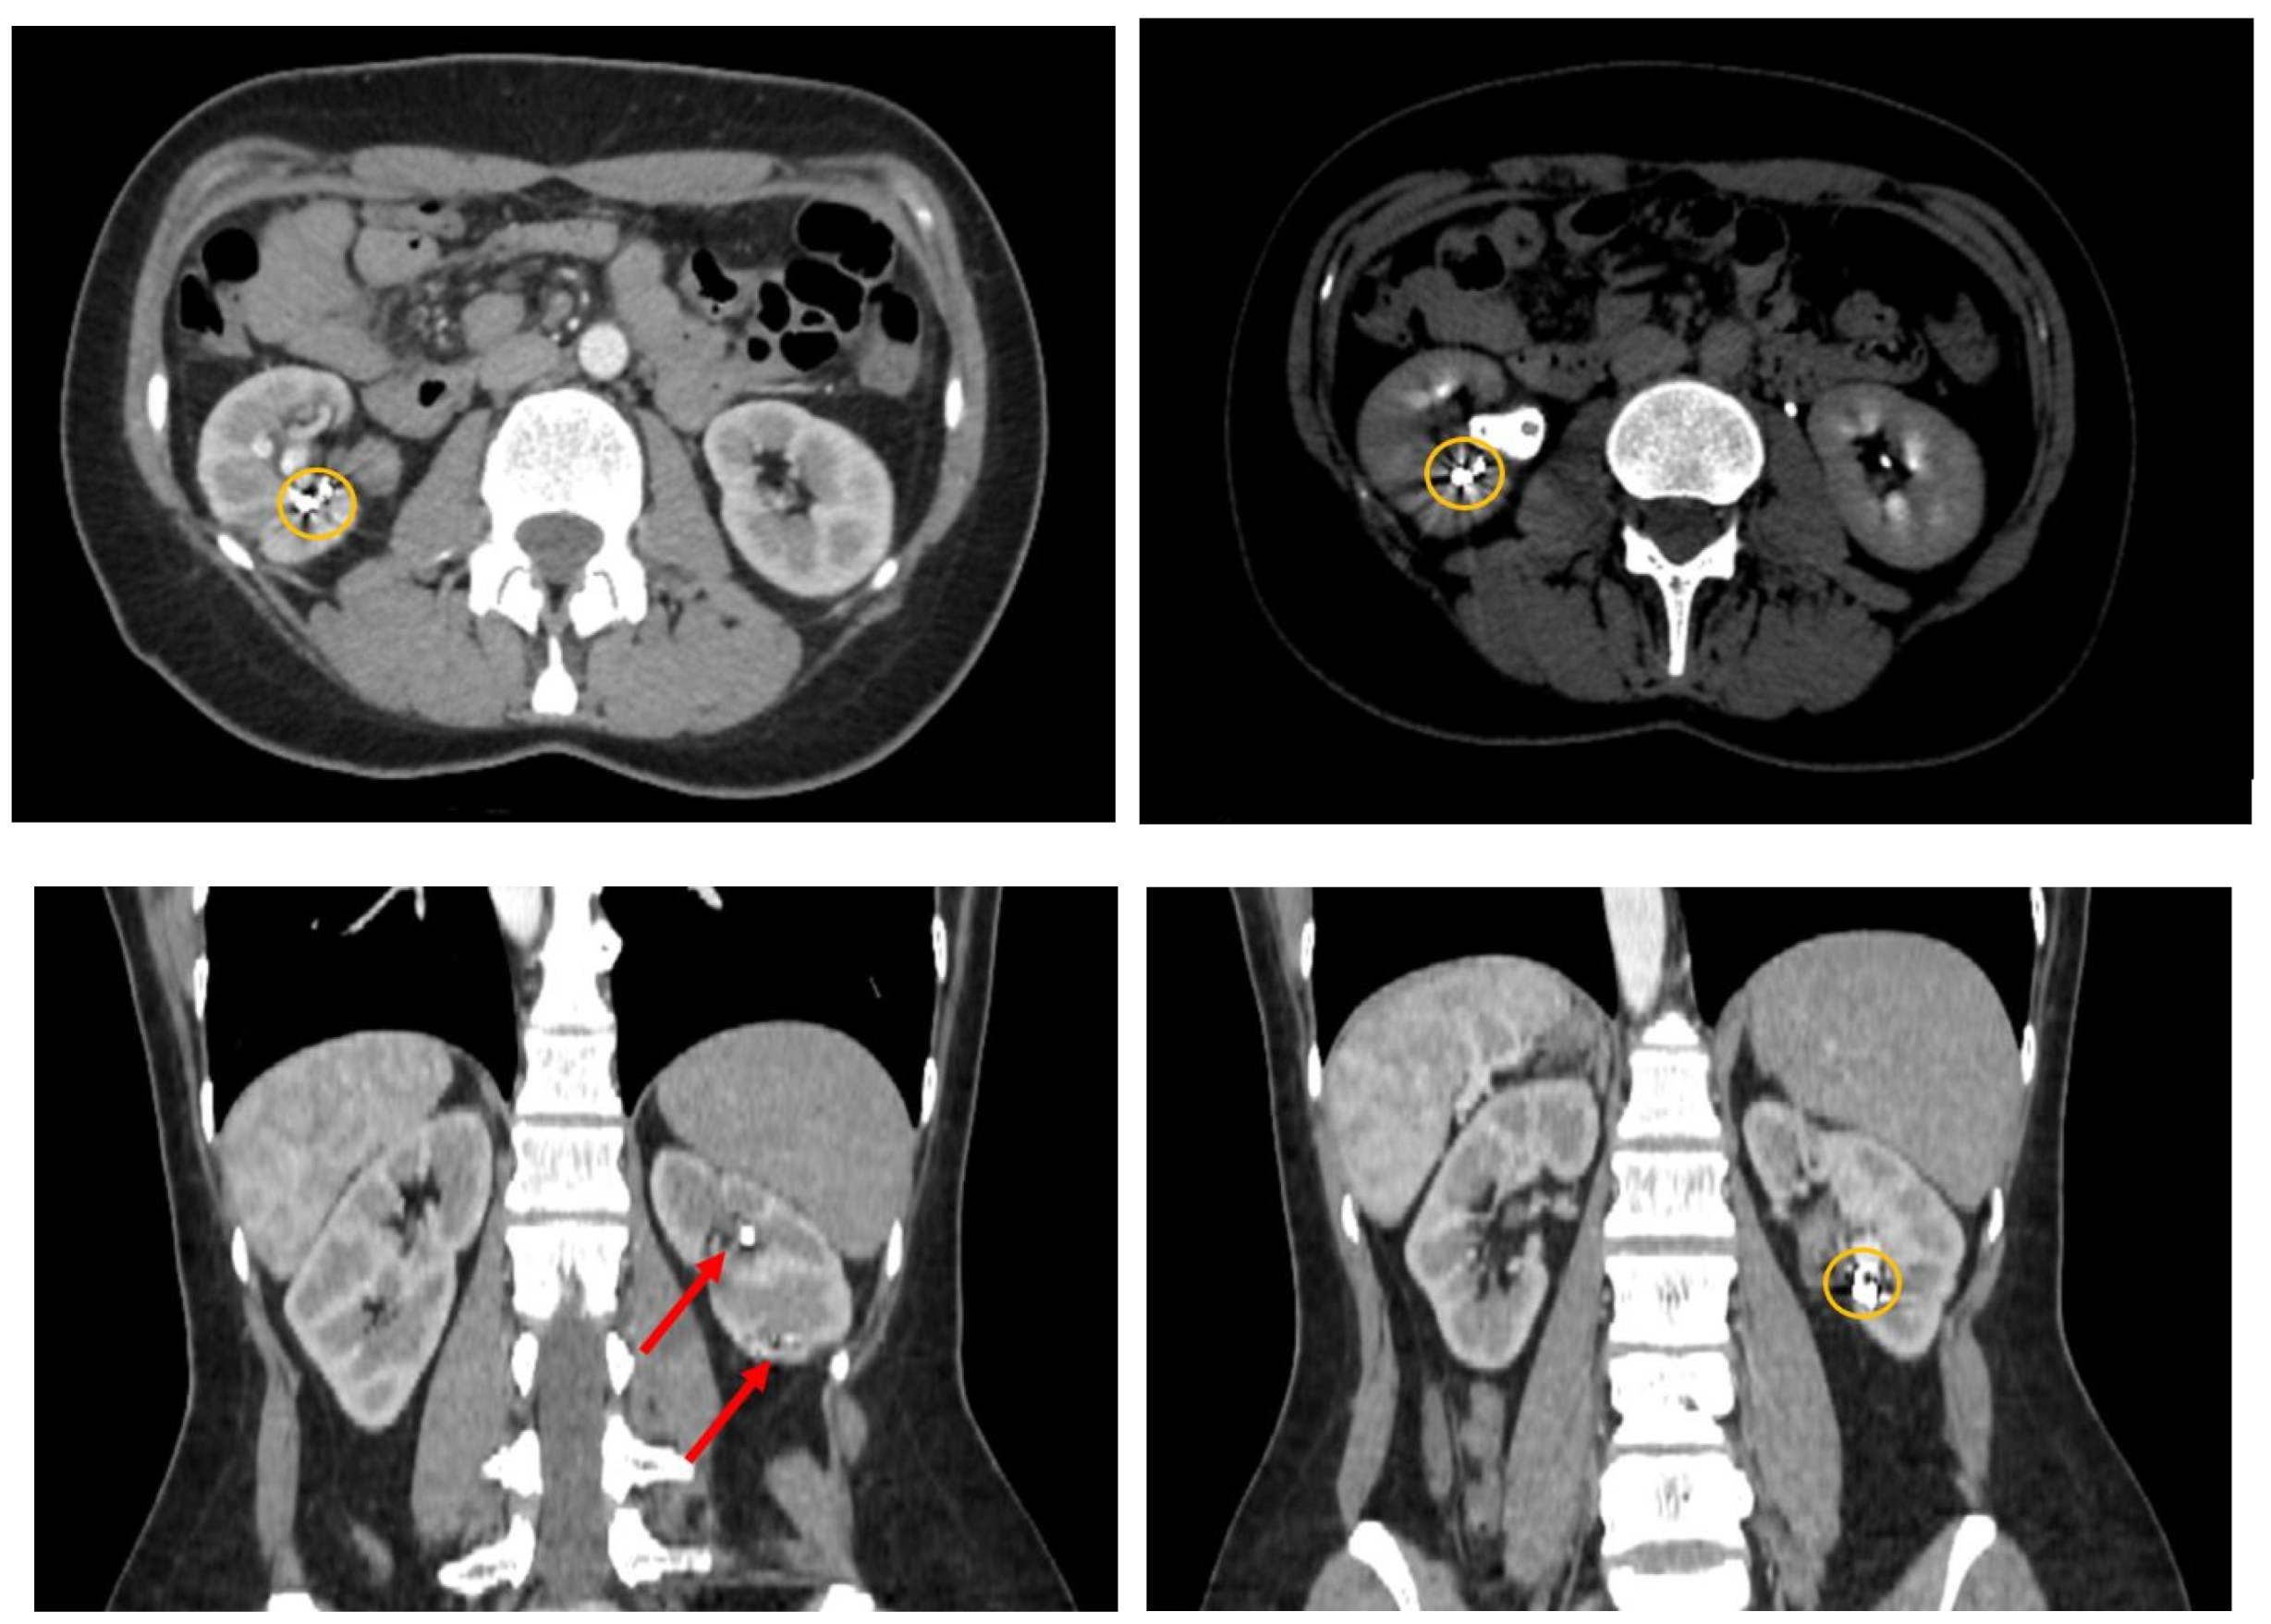

Following the cystoscopy, a contrast-enhanced computed tomography was performed to evaluate the abdomen and pelvic regions (Figure 2). The CT report indicated multiple hematic accumulations at various stages of degradation, predominantly recent (with average native densities of approximately 60 Hounsfield Units), within the right renal collecting system, without evidence of dilation. At the lower pole level, multiple pseudoaneurysm-like images were observed. These lesions appeared within the renal sinus, approximately 10mm in maximum diameter, and in intimate contact with the lower and middle calyceal stems. A series of metallic structures was identified, described in the report as clips (most probably the coils used during the last angioembolization). A small number of unobstructive stone fragments were also identified, with distribution in all the calyces and a maximum diameter of 5 mm.

Figure 2. Contrast-enhanced CT (axial and sagittal view) revealing multiple hematic accumulations at various stages of degradation (indicated by the orange circles) and lithiasis (indicated by the red arrows).